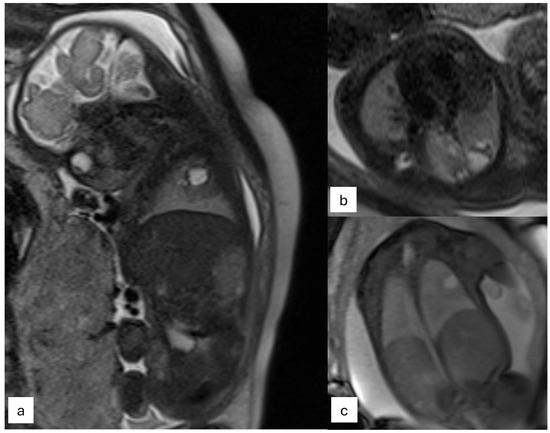

| Cardiac masses | -Assessment of function, size of mass, and relation to neighboring structures -Potential of tissue characterization -Renal and brain assessment in tuberous sclerosis |